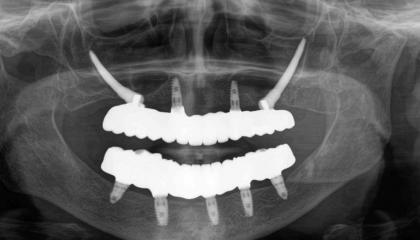

Zirconia bridge on Southern DC Implants

Tooth Replacement

Zirconia Implants